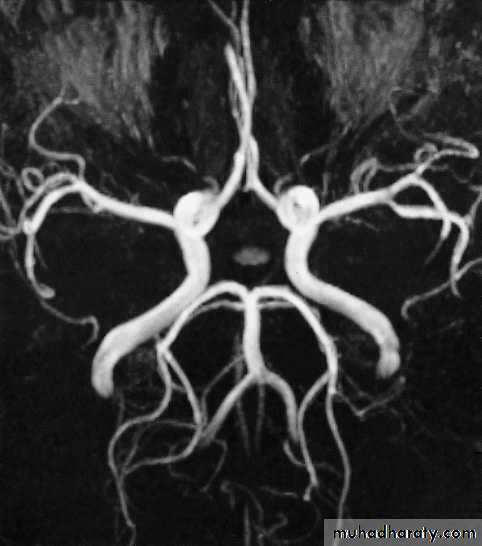

• IV contrast in T1 WI

• MRA and MRV, Recent advances of MRI: perfusion, diffusion, spectroscopy, functional MRI, and tractography